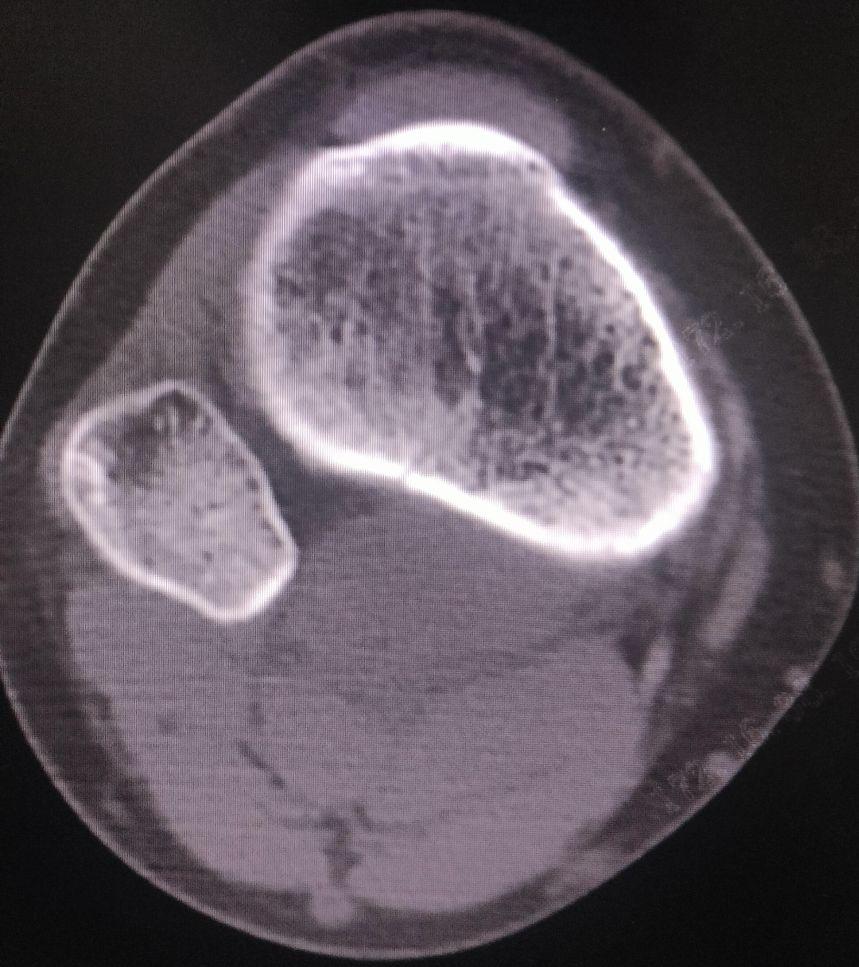

CT检查报告:

1.右胫骨平台髁间隆突骨折。

2.右膝关节腔积液。胸片:心肺膈肌未见明显异常。

右胫骨髁间棘骨折

诊断要点:1. 外伤史及典型症状。2. 体格检查:前抽屉试验、Lachman试验阳性,但终末点可能因骨块阻挡而变硬。3. 影像学检查:X线(侧位片最清晰)可见胫骨髁间前区撕脱骨片。CT可精确评估骨折移位程度,MRI可评估ACL韧带实质及合并损伤。